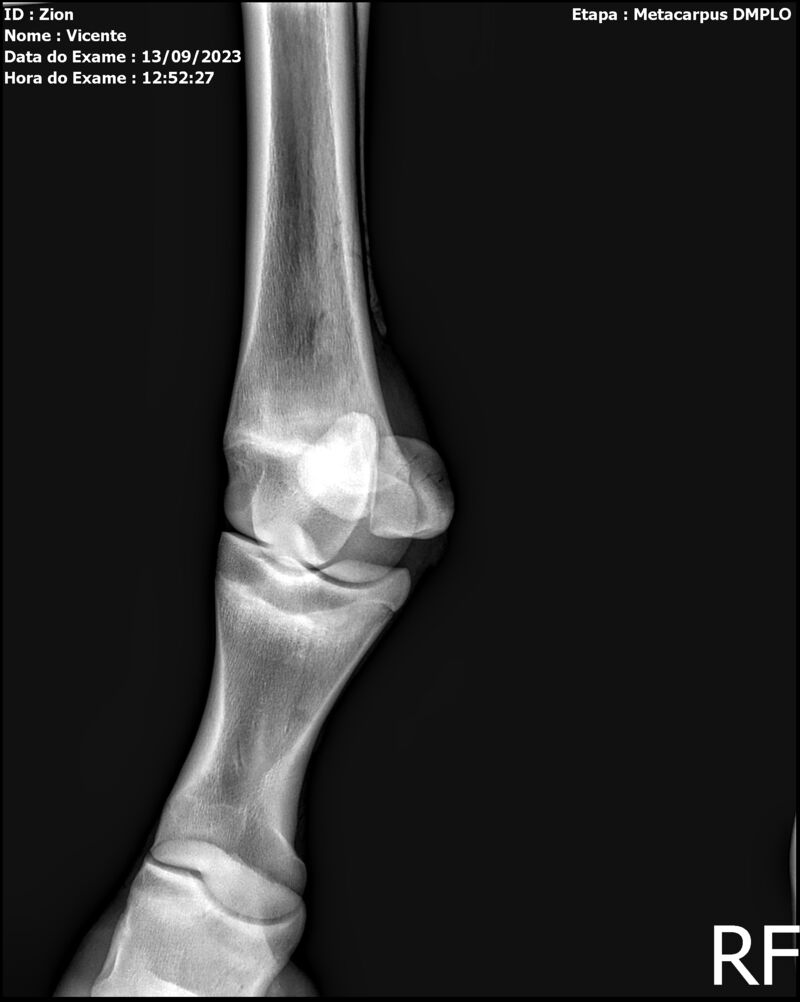

ZION ZC

Raça: BRASILEIRO DE HIPISMO

Sexo: MACHO - POTRO

Nascimento: 17/12/2022

Altura Aproximada: 1,51

Pel.: CASTANHO

Registro: EM AND

Vend.: VICENTE CONTE

Local : PORTO FELIZ/SP